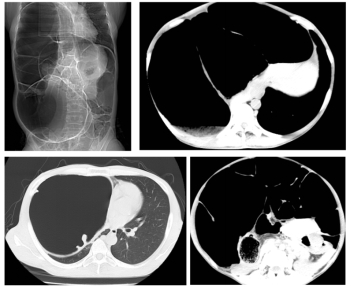

家住佳木斯40岁的陈女士,被便秘困扰20余年,长期遭受便秘的折磨,近年间症状持续加重,排便周期长达7日并伴随剧烈腹胀。陈女士在ac米兰官网中文网站附属第一医院群力院区行CT检查,腹腔内盲肠、升结肠、横结肠、降结肠及部分乙状结肠严重扩张积气,移行段位于乙状结肠,以造成右侧膈肌上移压迫右肺。群力院区普外科一病房(结直肠外科)朱跃坤教授诊断为特发性巨结肠。